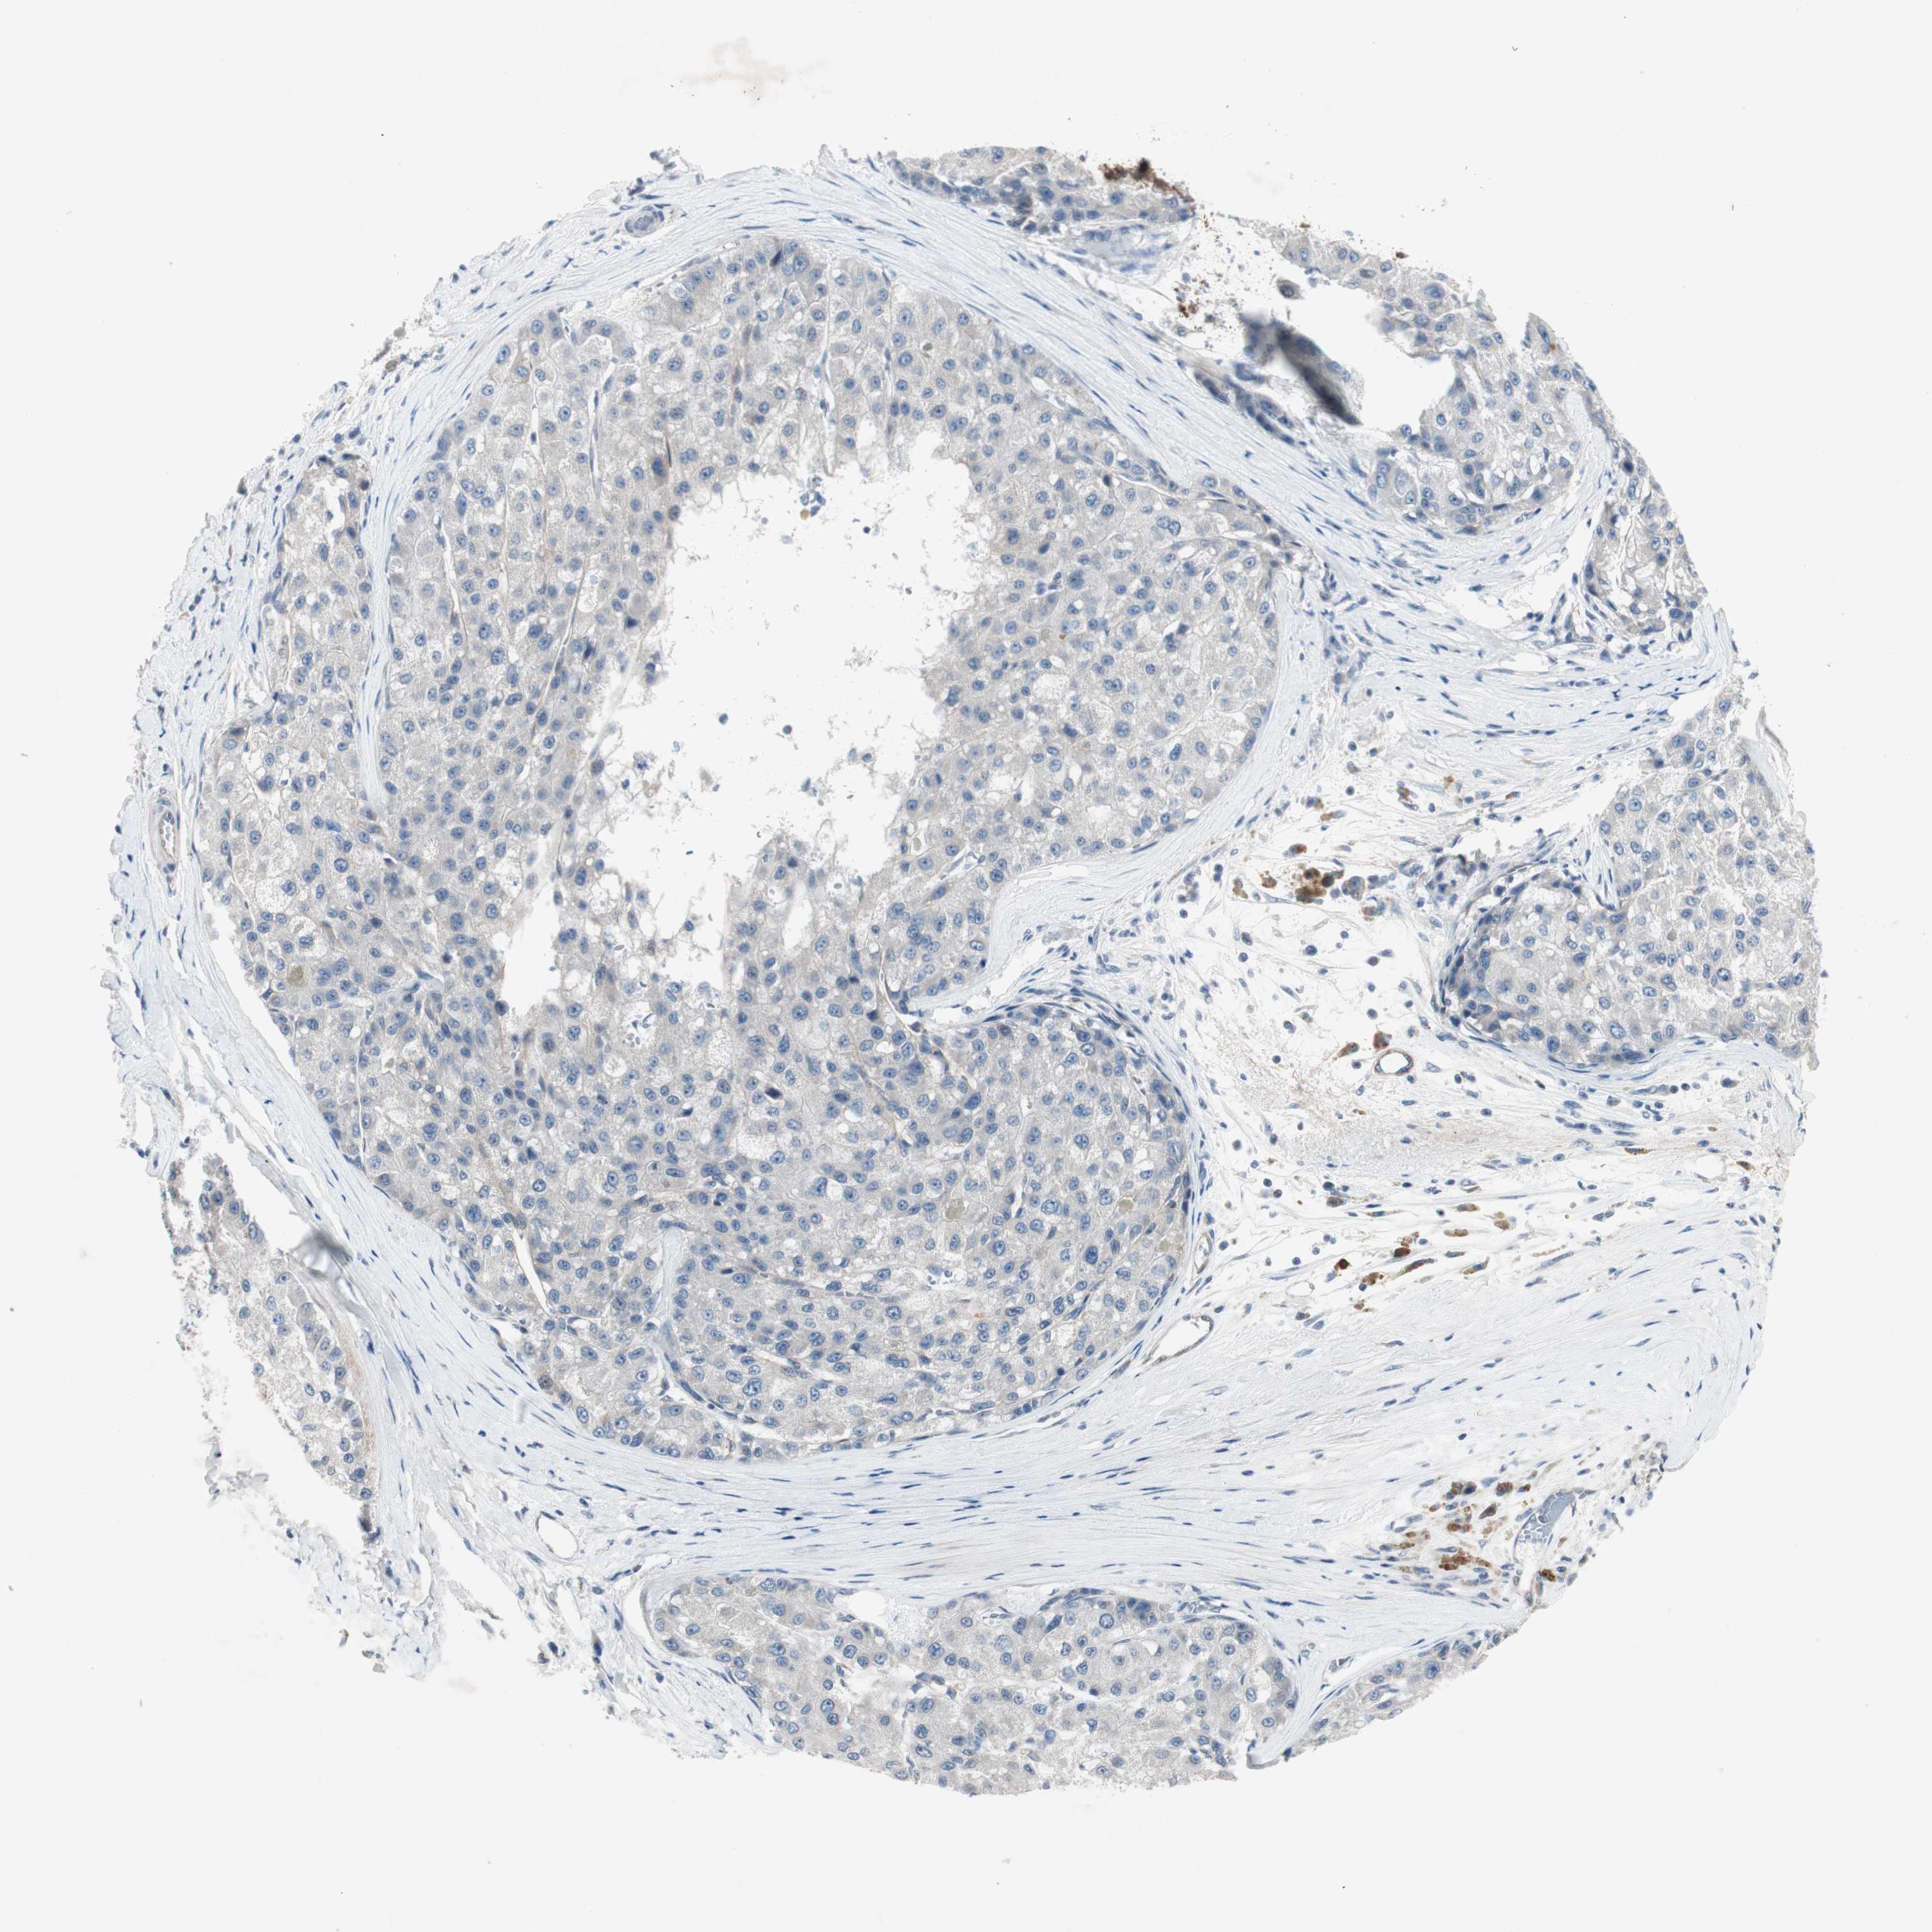

LIVER CANCER - Protein expressioni

A mouse-over function shows sample information and annotation data. Click on an image to view it in a full screen mode. Samples can be filtered based on level of antibody staining by selecting one or several of the following categories: high, medium, low and not detected. The assay and annotation is described here.

Note that samples used for immunohistochemistry by the Human Protein Atlas do not correspond to samples in the TCGA dataset.

Antibody stainingi

Antibody staining in the annotated cell types in the current human tissue is reported as not detected, low, medium, or high, based on conventional immunohistochemistry profiling in selected tissues. This score is based on the combination of the staining intensity and fraction of stained cells.

Each image is clickable and will lead to virtual microscopy that enables deeper exploration of all samples and also displays staining intensity scores, fraction scores and subcellular localization as well as patient and tissue information for each sample.

Antibody HPA036348

Antibody HPA036349

Antibody CAB002422

Antibody CAB005258

Staining

High

Medium

Low

Not detected

Intensity

Strong

Moderate

Weak

Negative

Quantity

>75%

75%-25%

<25%

None

Location

Nuclear

Cytoplasmic/membranous

Cytoplasmic/membranous,nuclear

Cholangiocarcinoma

Carcinoma, Hepatocellular, NOS